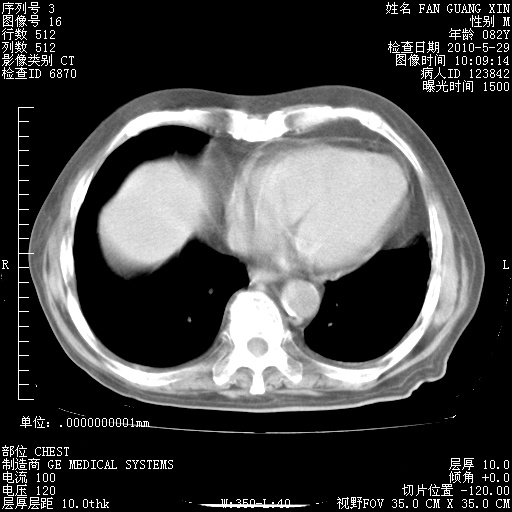

再治疗10天后的肺部CT 纵膈窗